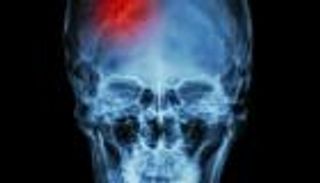

اختراع قفاز لعلاج تبعات السكتة الدماغية

تؤدي السكتات الدماغية غالباً إلى تأثير مدمّر على وظيفة اليدين، ما جعل الباحثين في جامعة ستانفورد يتعاونون حالياً، بغية إنتاج قفاز يحسن وظيفة اليد بعد الإصابة بالمرض.

ويفقد الناجون من موت السكتات الدماغية عادةً قدرة الإحساس والتحكم في عضلات إحدى اليدين، ما يُعقّد من المهمات اليومية مثل ارتداء الملابس والأكل واستخدام فرشاة الأسنان أو مقبض الباب.